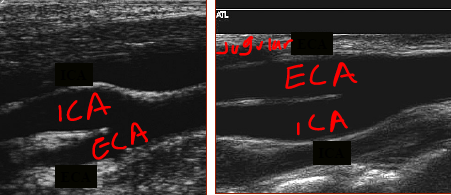

how can you differentiate the ICA from the ECA by anatomy and in the waveforms?

Anatomy:

posterior position of ICA (usually 95% of the time)

branches of ECA - no one cares about this it never gets treated.

ICA size: not reliable when diseased

Doppler waveforms & sounds:

ICA = low resistance

ECA = high resistance

*first branch off of ICA is superior thyroid (cervical branches)

ECA position, whether lateral, anterior or medial, is _____.

variable

is it possible for the ICA to lie deep or superficial to the ECA?

yes.

ICA is ____ resistance

ECA is ____ resistance

they both flow _____ the head

low

high

towards